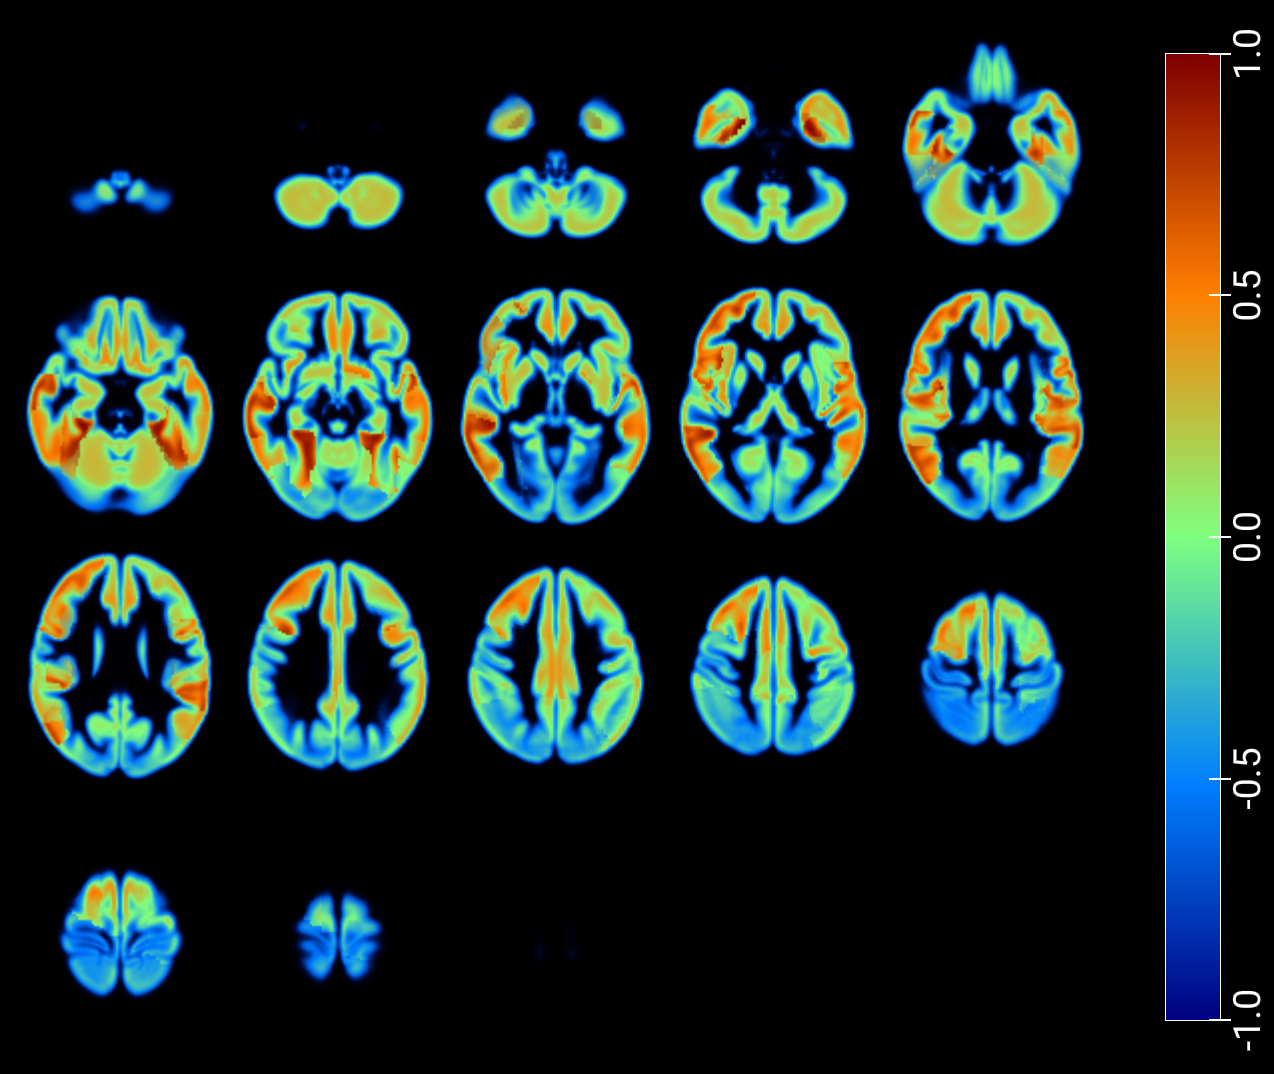

As a critical baseline, we report classification results based on latent features in [2] and provide visualizations of the maximum Pearson correlation values between latent-space activations -projected onto low-dimensional spaces- and region-wise average intensities, stratified by class, and fused with GM MRI (figures 7 and 8). These results explore the correspondence between network activations and anatomical signal distributions and whether it differs across clinical conditions (e.g., AD vs. NOR). This offers a transparent alternative to assess model interpretability and underscores the need for more rigorous and nuanced validation practices in the field.

An inspection of the groups and regions with the highest correlations reveals overlapping areas across clinically relevant comparisons in image reconstruction, as summarized for the t-SNE–based projections in Table 2. These regions correspond closely to those identified through the SHAP analysis presented in the following section (Table 3).

Finally, we applied the Latent–Regional Correlation Profiling (LRCP) framework to generate spatial maps that highlight how latent components relate to regional brain variation across different diagnostic comparisons. Specifically, we focused on the three binary groups and, for each case, projected the regional accuracy of the latent–region associations onto an anatomical atlas. By computing corrected significance rates for each latent–region pair and averaging them across subjects, we obtained accuracy maps that indicate which brain regions consistently encode discriminative information for each comparison. These maps provide an interpretable visualization of the spatial distribution of diagnostic relevance, facilitating a region-wise comparison of how latent dimensions capture biologically meaningful variation across the different binary groups.